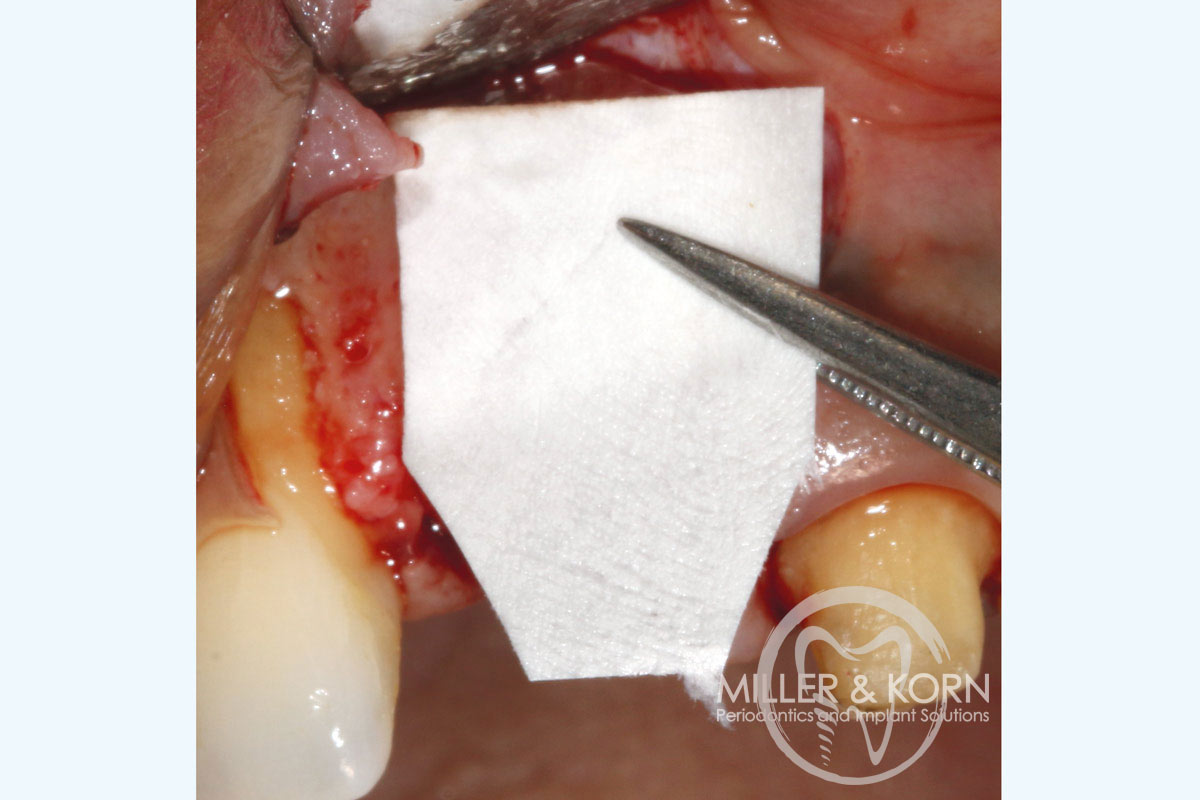

13/22 - Cutting the membrane to the appropriate shape.Immediate implant placement and regeneration of ridge using an allograft bone ring and Jason® membrane - Drs. Miller and Korn

14/22 - Covering the site with bone substitute and Jason® membrane.Immediate implant placement and regeneration of ridge using an allograft bone ring and Jason® membrane - Drs. Miller and Korn